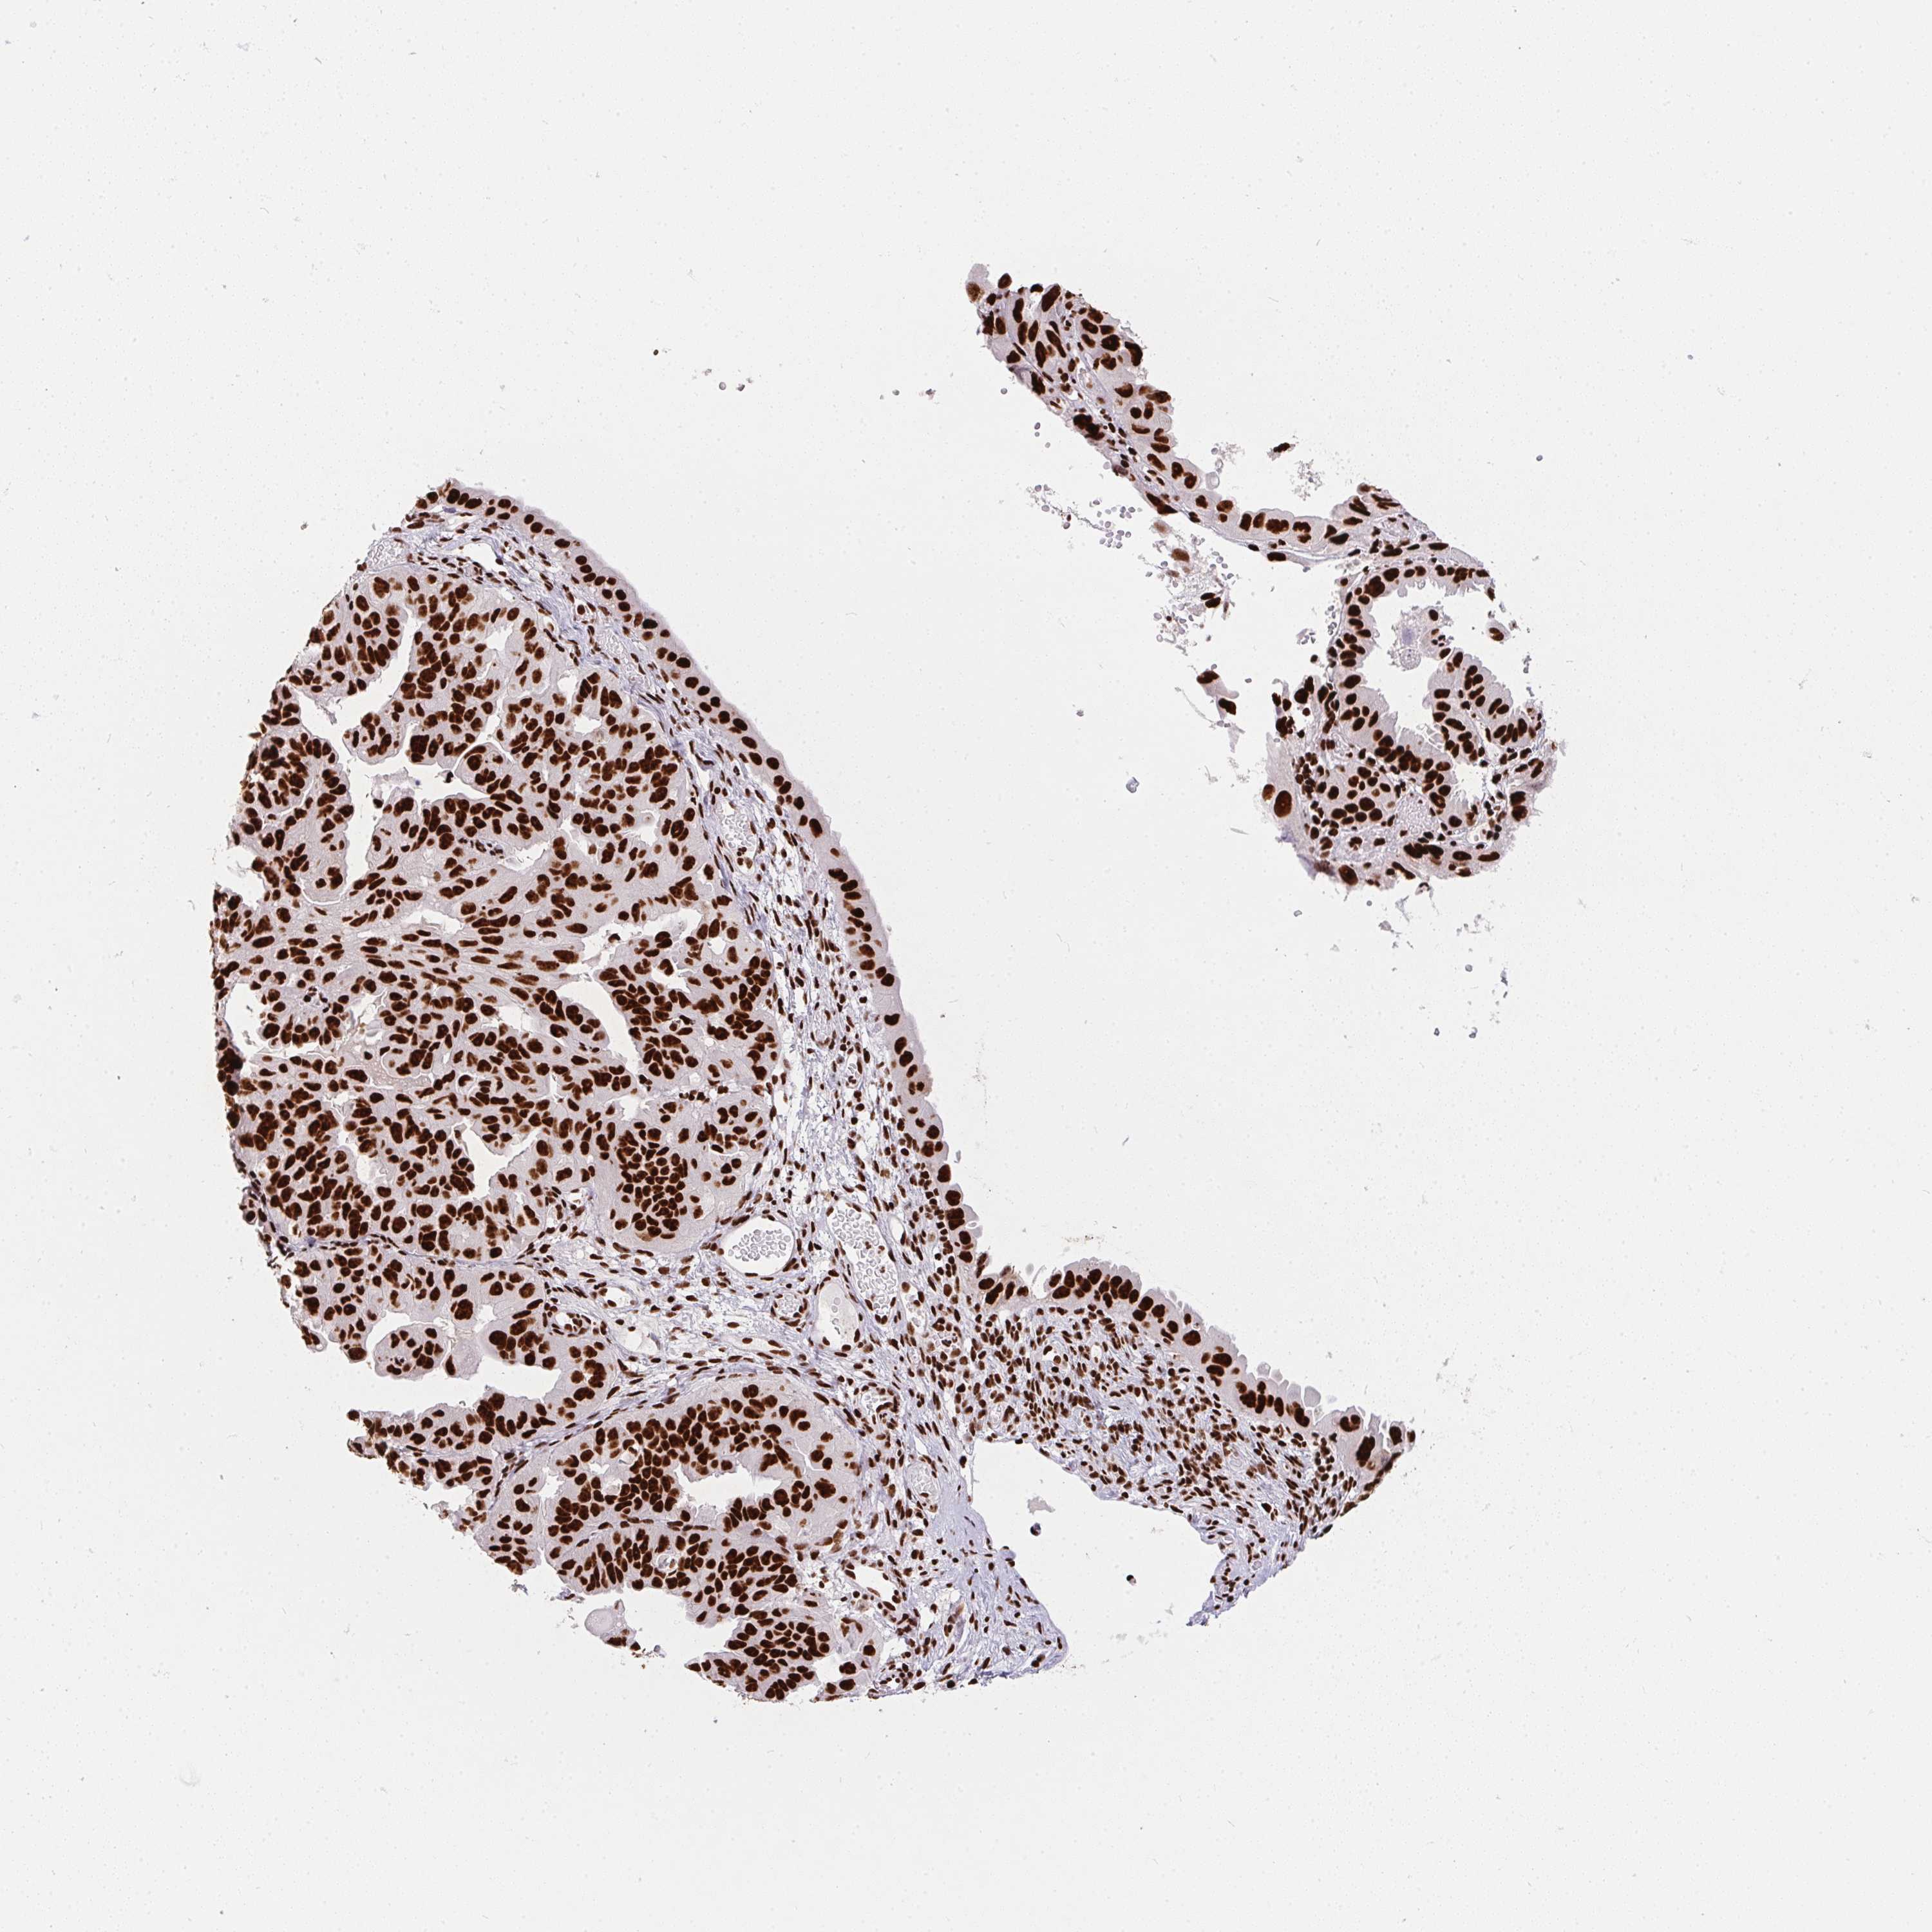

OVARIAN CANCER - Protein expressioni

A mouse-over function shows sample information and annotation data. Click on an image to view it in a full screen mode. Samples can be filtered based on level of antibody staining by selecting one or several of the following categories: high, medium, low and not detected. The assay and annotation is described here.

Note that samples used for immunohistochemistry by the Human Protein Atlas do not correspond to samples in the TCGA dataset.

Antibody stainingi

Antibody staining in the annotated cell types in the current human tissue is reported as not detected, low, medium, or high, based on conventional immunohistochemistry profiling in selected tissues. This score is based on the combination of the staining intensity and fraction of stained cells.

Each image is clickable and will lead to virtual microscopy that enables deeper exploration of all samples and also displays staining intensity scores, fraction scores and subcellular localization as well as patient and tissue information for each sample.

Antibody HPA062248

Staining

High

Medium

Low

Not detected

Intensity

Strong

Moderate

Weak

Negative

Quantity

>75%

75%-25%

<25%

None

Location

Nuclear

Cytoplasmic/membranous

Cytoplasmic/membranous,nuclear

Cystadenocarcinoma, serous, NOS

Cystadenocarcinoma, mucinous, NOS

Carcinoma, endometroid